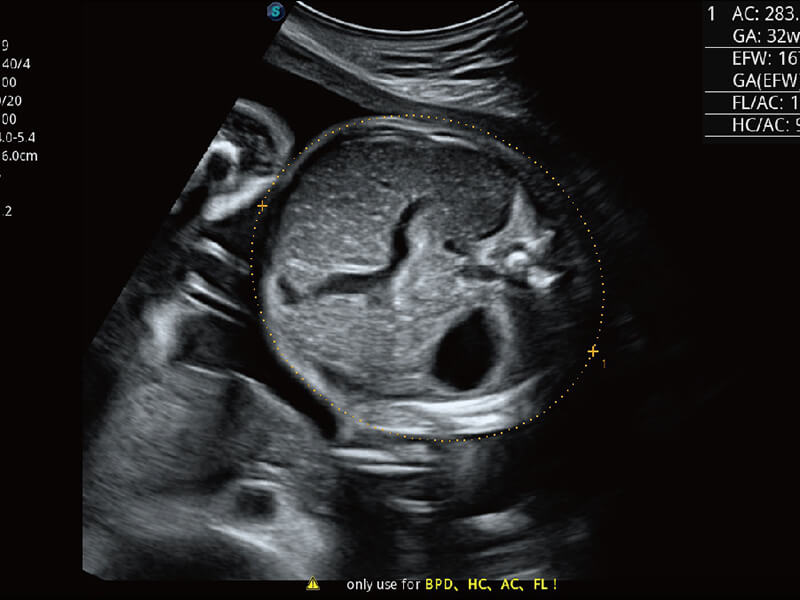

S60创新的探头工艺、高精度模数转换系统、前沿的波束重建技术,从前端信号处理每一个环节采集无损声学数据,真实还原组织原貌,再现解剖细节。

创新的超宽频带技术,为容积成像带来优质的二维图像基础,为您呈现更丰富的结构细节,栩栩如生地展示宝宝的宫内形态以及各种组织的立体结构。